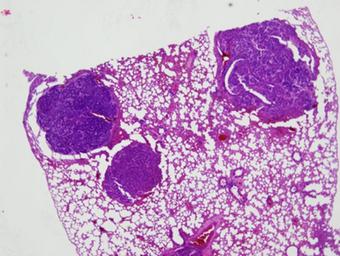

MAKE A MEME View Large Image Genetic engineering; DNA repair (5880423037).jpg Section of lung tissue from a double knockout mouse stained to show lung tumors Mice lacking both the neil1 and nth1 genes were particularly prone to pulmonary anbd liver tumors during their ...

Keywords: Genetic engineering; DNA repair (5880423037).jpg Section of lung tissue from a double knockout mouse stained to show lung tumors Mice lacking both the neil1 and nth1 genes were particularly prone to pulmonary anbd liver tumors during their second year Credit Teebor/NYU Disclaimer Any mention of commercial products within NIST web pages is for information only; it does not imply recommendation or endorsement by NIST Use of NIST Information These World Wide Web pages are provided as a public service by the National Institute of Standards and Technology NIST With the exception of material marked as copyrighted information presented on these pages is considered public information and may be distributed or copied Use of appropriate byline/photo/image credits is requested https //www flickr com/photos/usnistgov/5880423037/ Genetic engineering; DNA repair 2009-06-30 15 55 https //www flickr com/people/63059536 N06 National Institute of Standards and Technology PD-USGov National Institute of Standards and Technology https //flickr com/photos/63059536 N06/5880423037 2016-09-07 02 51 44 United States Government Work Uncategorized 2016 October 23